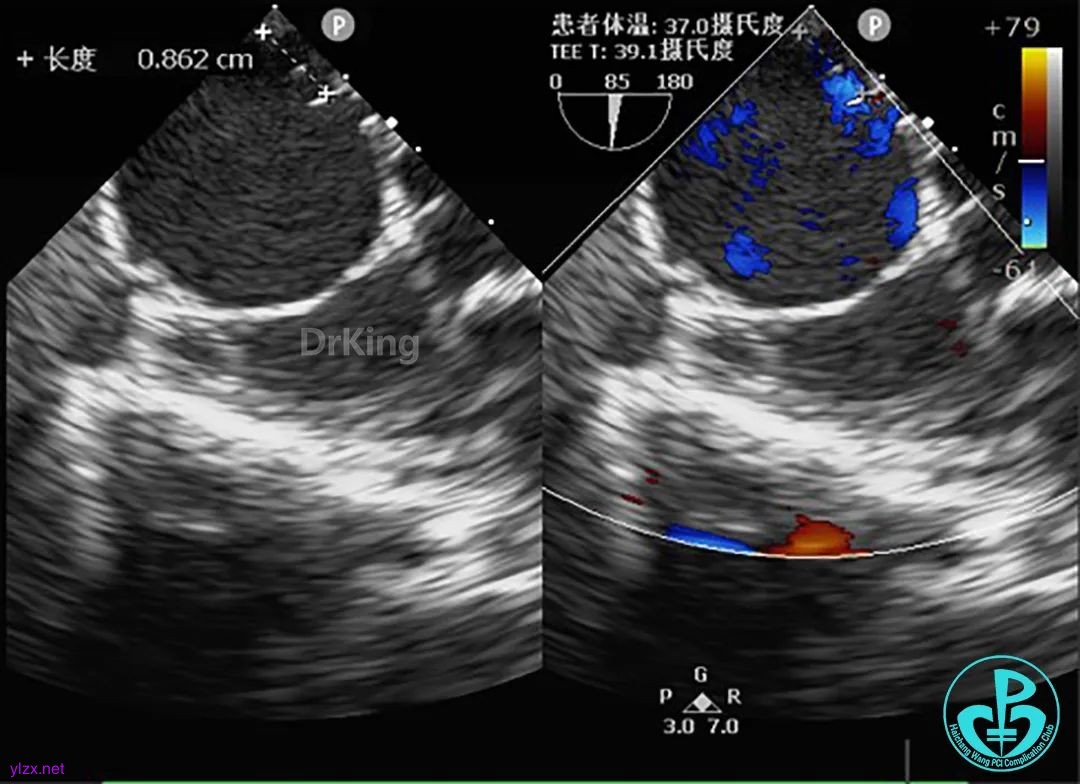

术中经食道超声复测缺损大小为8.62mm。

患儿年纪尚小,仅有8个月,考虑到美观度、安全性以及术后恢复速度,选用纯超声引导腋下经胸微创路径,故综合术中复测值与术前超声报告,选择BDASD-Ⅱ 14可降解ASD封堵器封堵缺损。